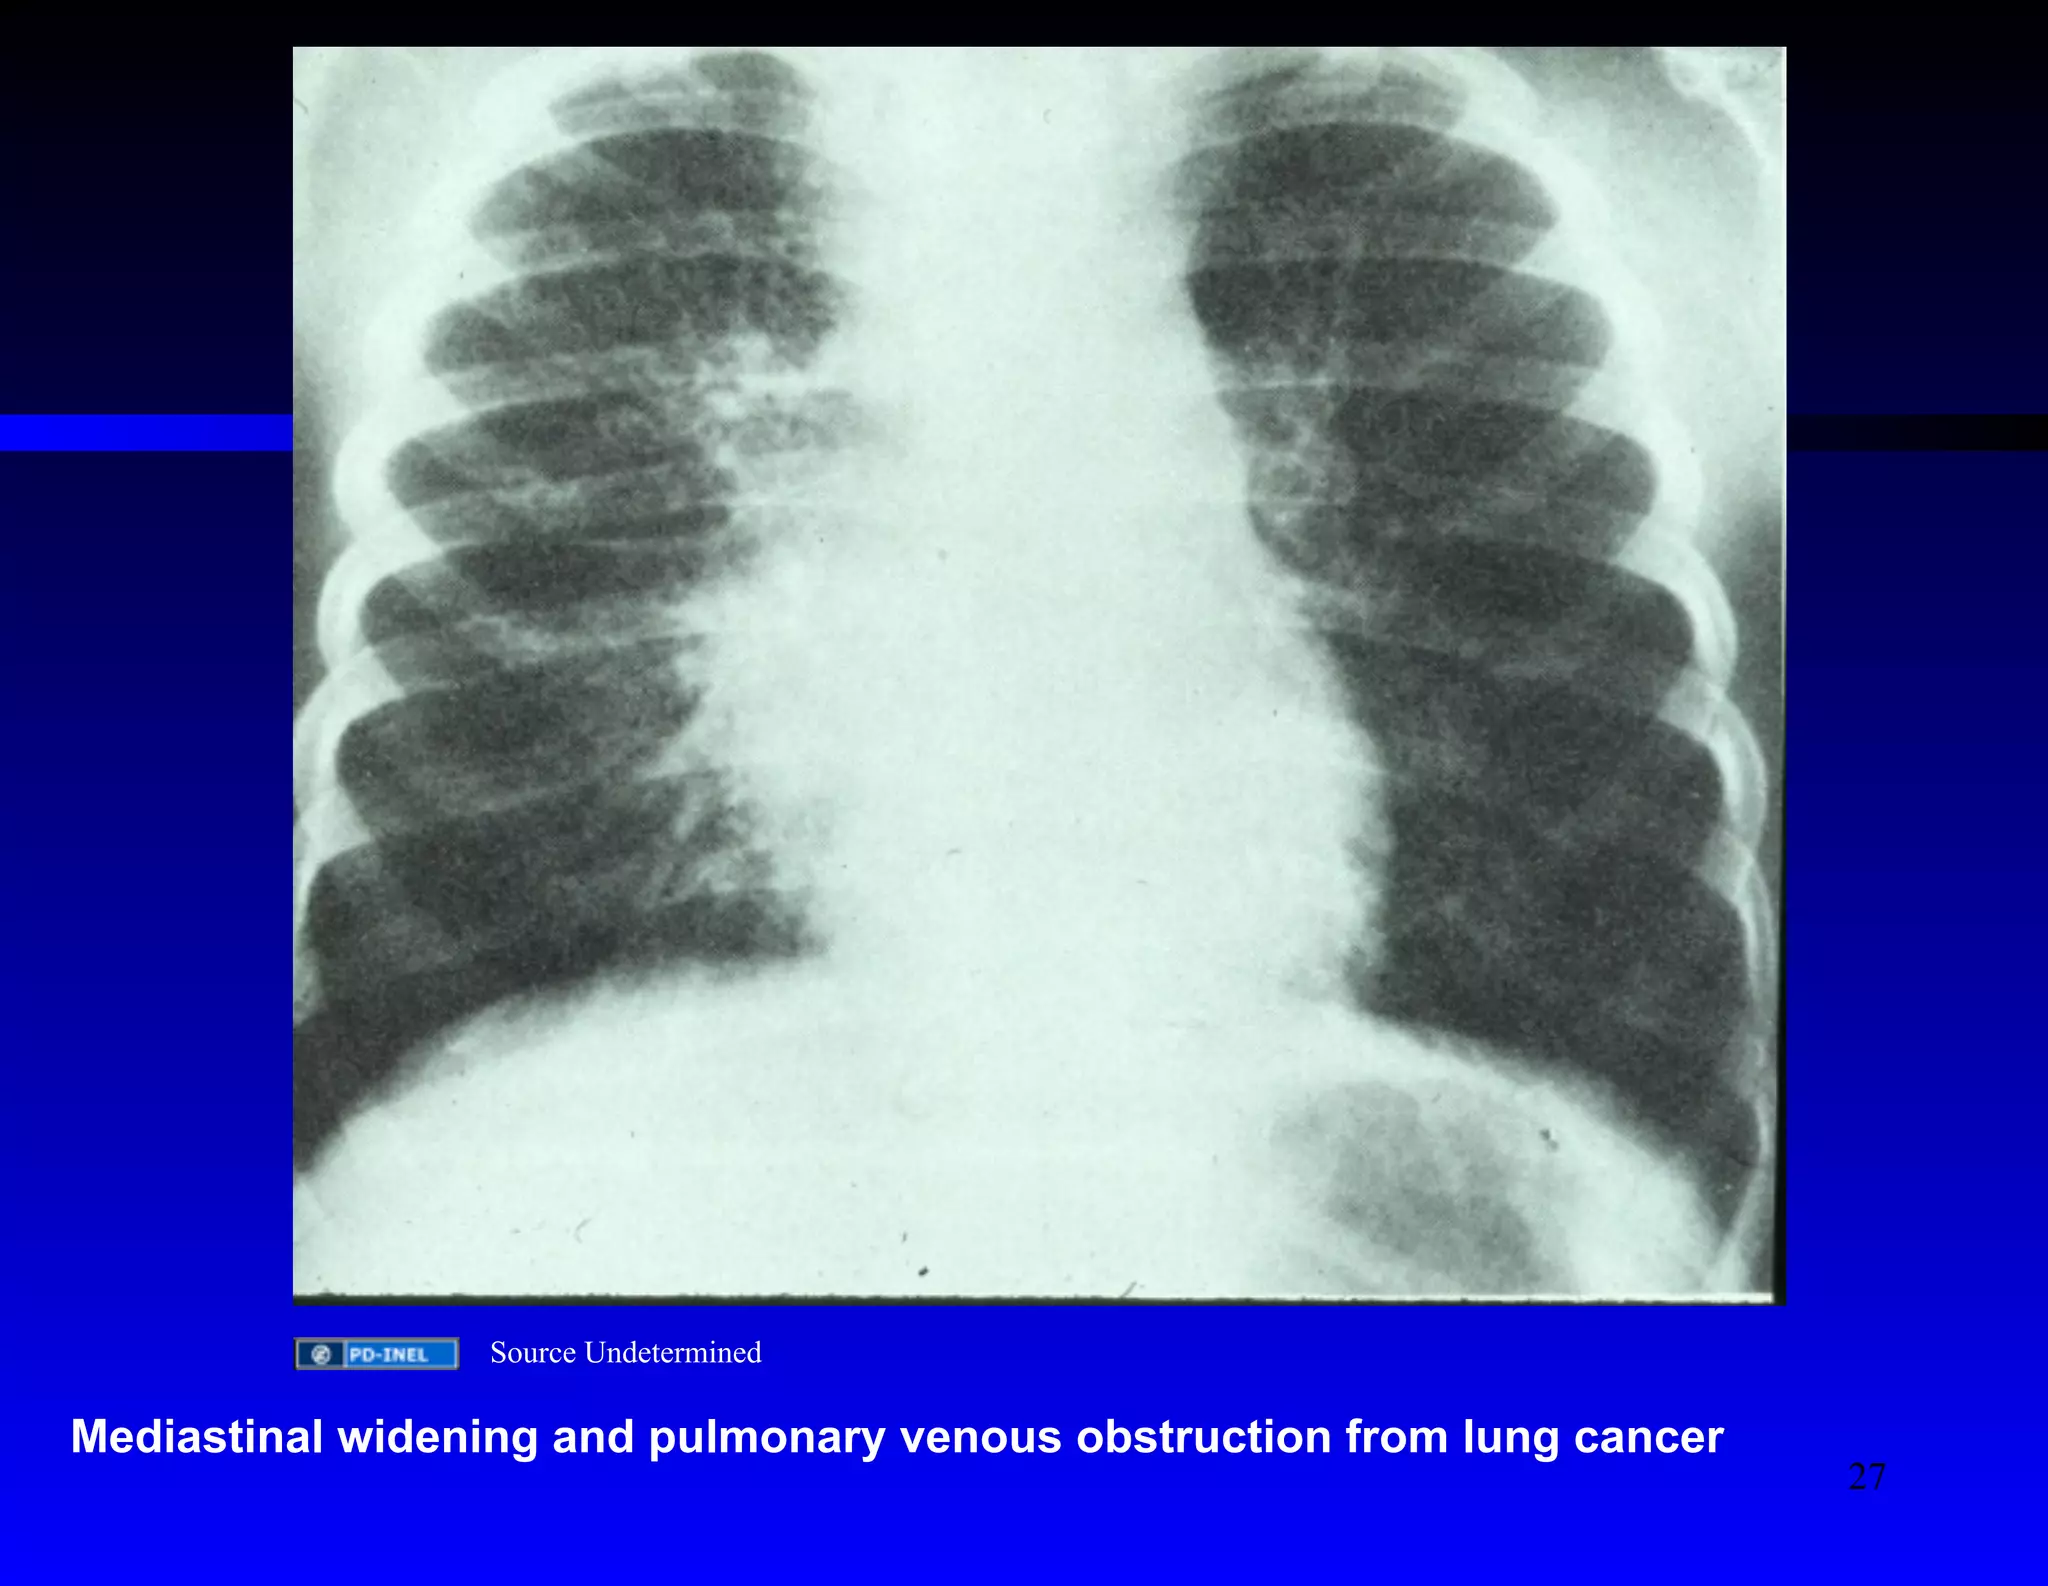

Source Undetermined

Mediastinal widening and pulmonary venous obstruction from lung cancer